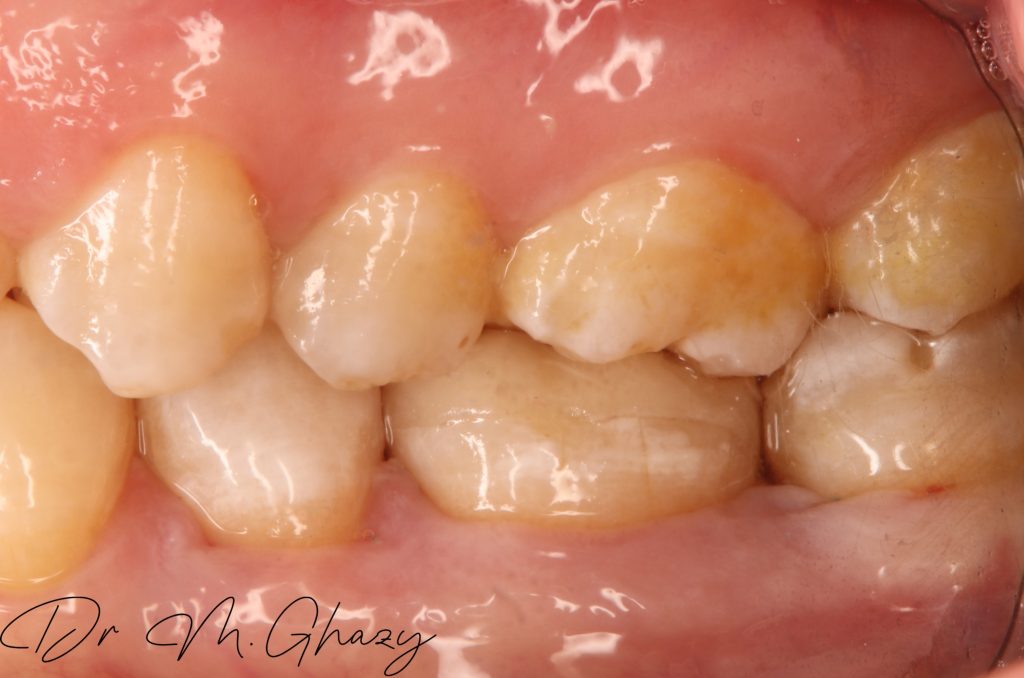

Per-operave occlusal

Occlusal clearance